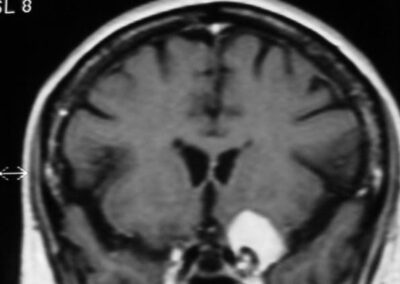

Signos y exámenes

El examen muestra, a menudo, signos neurológicos generales o focales que son específicos del sitio del tumor. Algunos tumores no muestran síntomas hasta que ya son bastante grandes y causan rápido deterioro neurológico, mientras que otros se caracterizan por los síntomas progresivos lentos. La mayoría de los tumores muestra signos típicos de masas que ocupan espacio (lesión ocupante de espacio: LOE), los cuales causan aumento de la presión intracraneal y compresión del tejido cerebral.

El diagnóstico se puede confirmar y el tumor localizar mediante:

• TAC cerebral

• RM cerebral